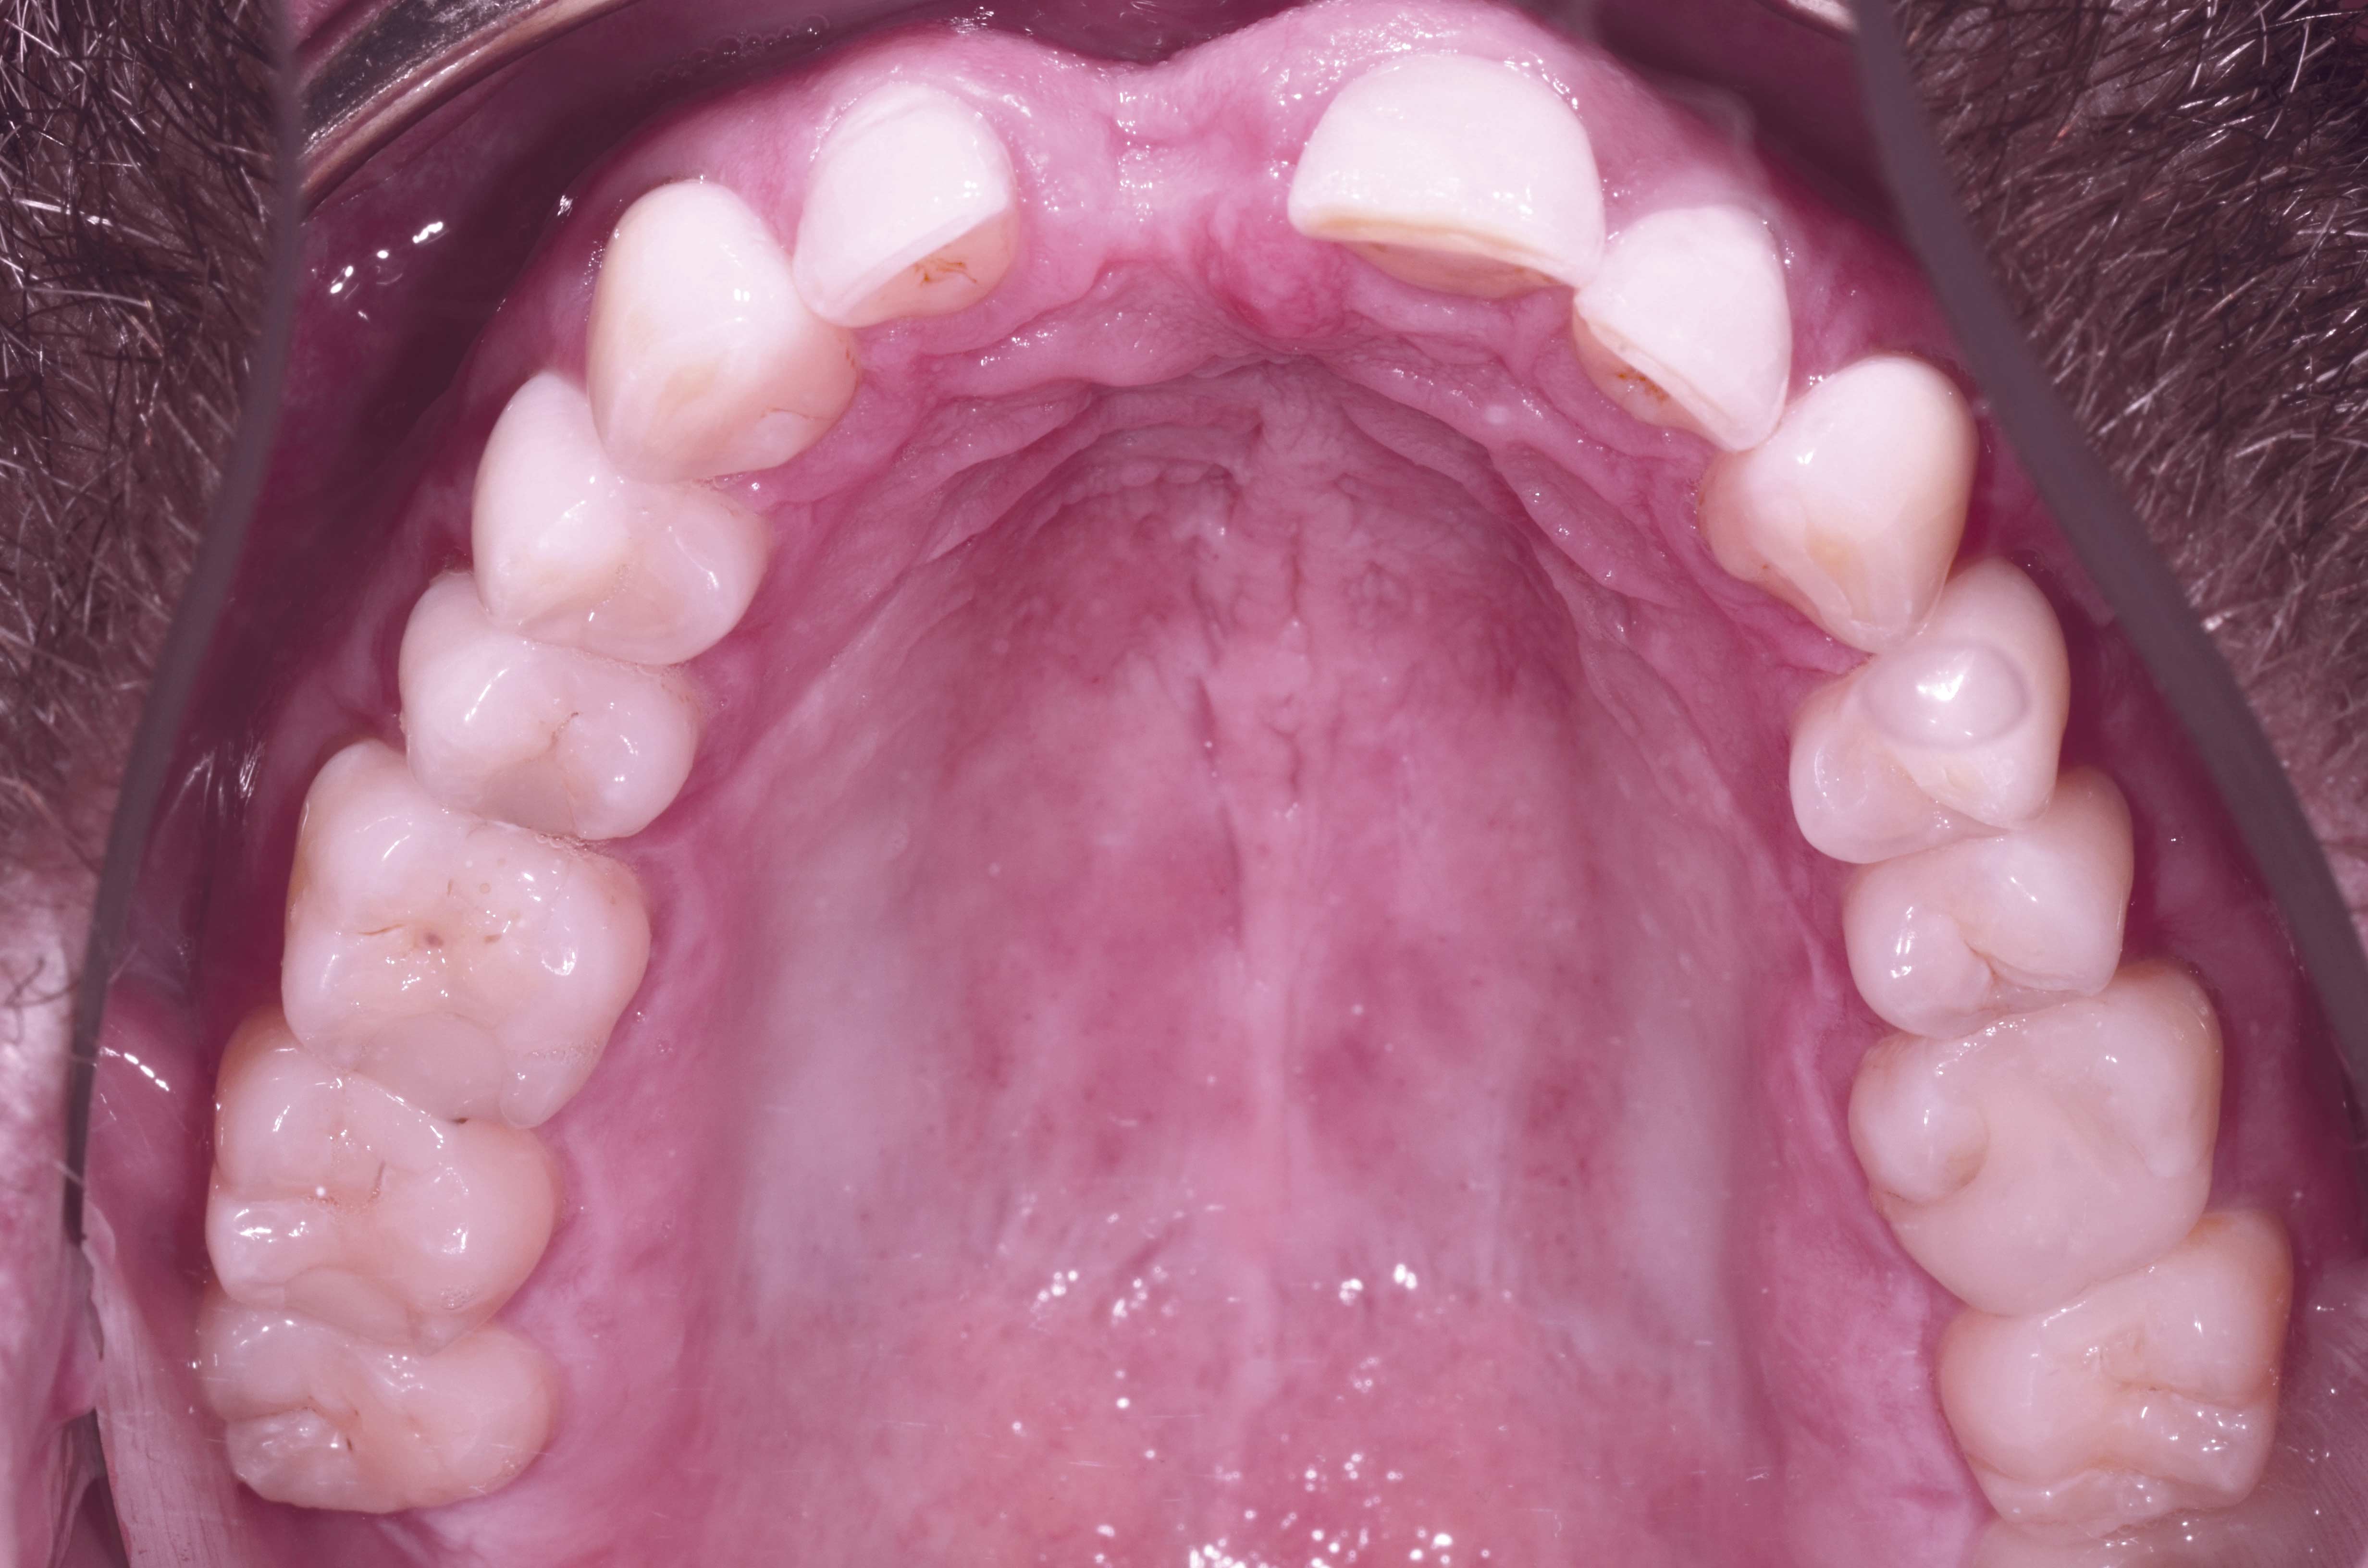

18/18 - Prosthetics 1 year after uncovering the implant

Block augmentation with maxgraft® and cerabone® – PD Dr. Dr. F. Kloss